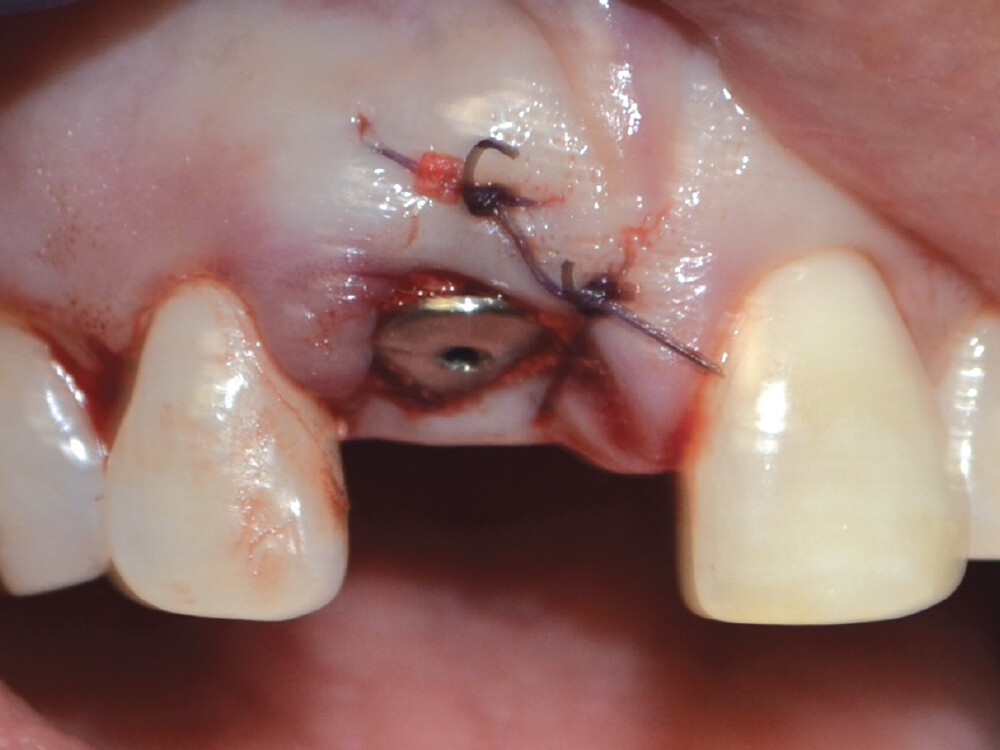

After the tooth was extracted, the site was thoroughly curetted. A pilot drill was used to begin the osteotomy, which was enlarged to the correct size for the implant. Prior to placing the implant, OsteoGen strip alloplast was re-hydrated with sterile saline and then placed in the socket against the wall adjacent to the gap. Hahn™ Tapered Implant (Glidewell Direct; Irvine, Calif.) was driven into place, and the graft material filled the gap. A healing abutment was placed and the site sutured with a Reli® REDISORB® PRO PGA 4-0 suture.